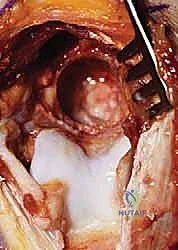

سُميت هذه العملية تيمناً بالجراحين اللذين قاما بتطويرها. تعتمد الفكرة الأساسية لهذه الجراحة العبقرية على مبدأ ميكانيكي بسيط ولكنه فعال للغاية. في الكوع المتيبس بسبب الخشونة، تتكون نتوءات عظمية في الجزء الأمامي (الناتئ الإكليلي والحفرة الإكليلية) والجزء الخلفي (الناتئ الزجي والحفرة الزجية).

بدلاً من إجراء شق جراحي أمامي وشق جراحي خلفي كبيرين للوصول إلى هذه النتوءات، يتم الوصول إلى المفصل من الخلف فقط. يقوم الدكتور هطيف بإزالة النتوءات العظمية الخلفية، ثم يقوم بـ إحداث ثقب (Fenestration) أو نافذة دقيقة في العظم الرقيق الفاصل بين الحفرة الزجية (الخلفية) والحفرة الإكليلية (الأمامية) لعظمة العضد.

هذا الثقب يحقق فوائد مذهلة:

1. يسمح للجراح بالرؤية والوصول إلى النتوءات العظمية الأمامية والأجسام الحرة وإزالتها من خلال هذا الثقب دون الحاجة لفتح الكوع من الأمام.

2. يخلق مساحة إضافية (فراغ) يسمح لطرف عظمة الزند بالدخول فيه أثناء فرد الكوع بالكامل، مما يزيل الاحتكاك ويزيد من نطاق الحركة فوراً.

3. يقلل الضغط داخل المفصل، مما يخفف الألم بشكل ملحوظ.